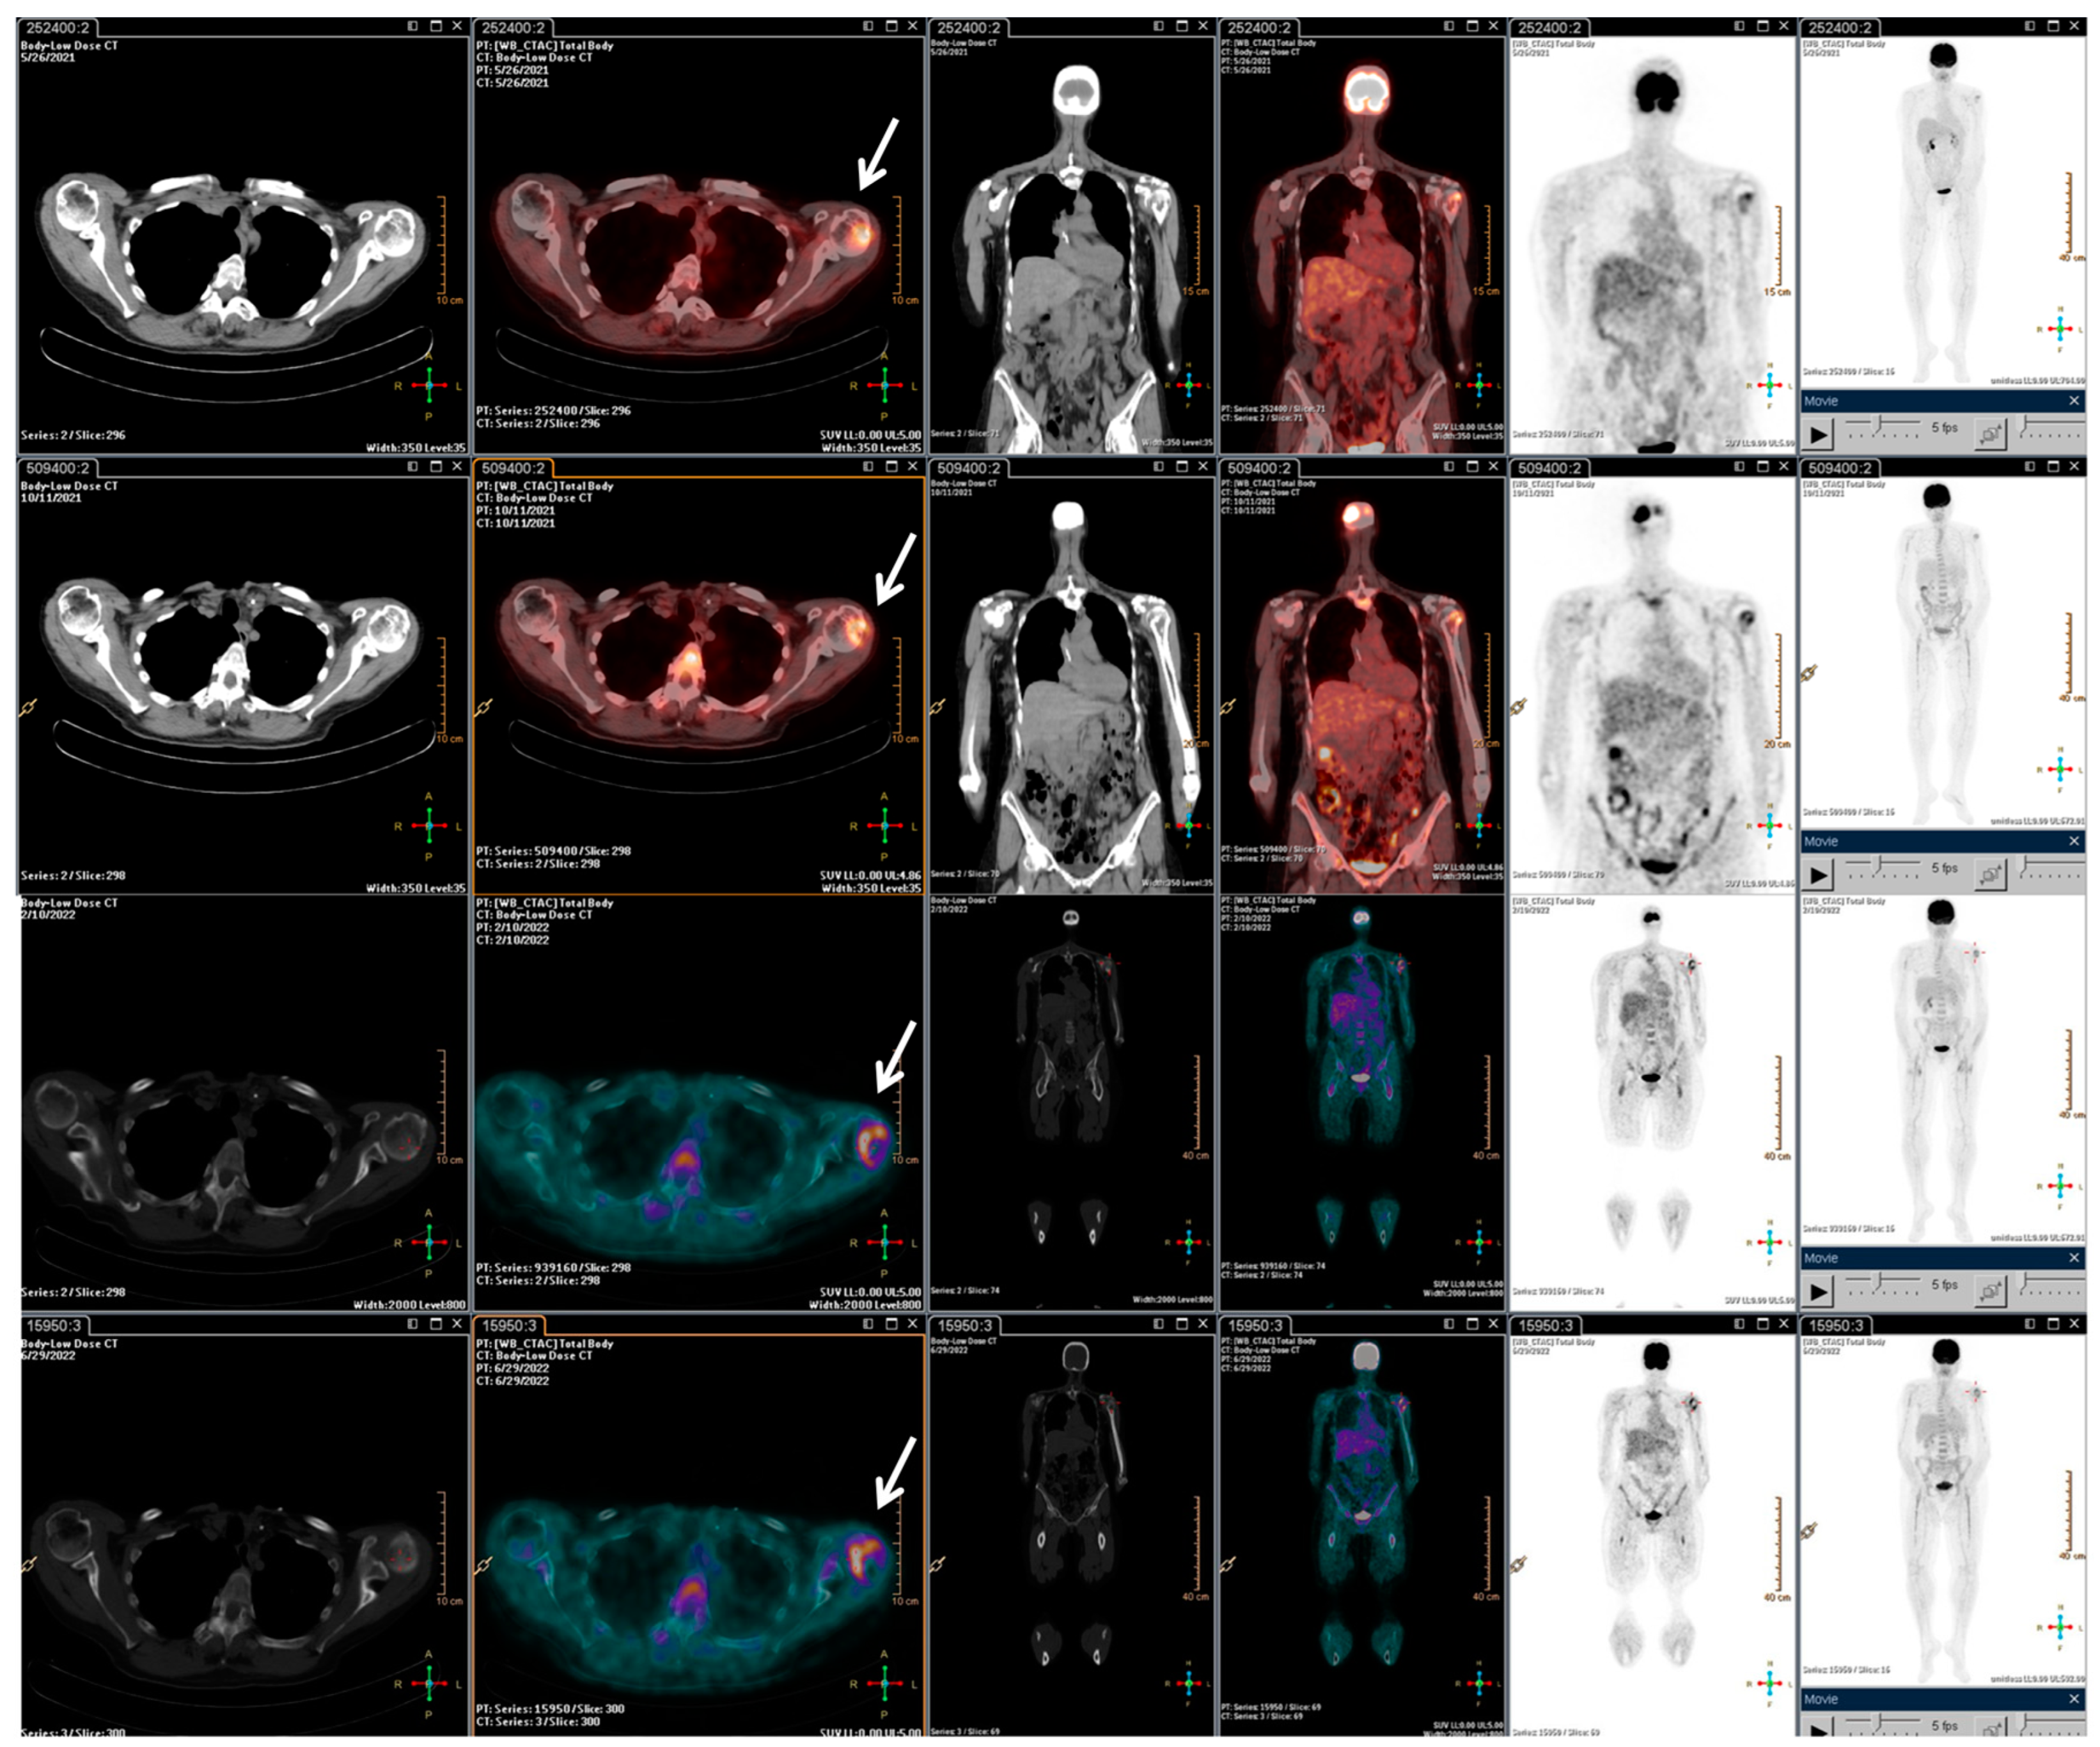

With the rising of the disease, trabectedin treatment was resumed and continued for an additional 21 cycles until January 2022, when a PET/CT scan revealed a slight metabolic progression in the left humeral head. Thus, in March 2022, radiotherapy treatment on the left humeral head was completed (20 Gy/5Fractions), and, considering the stable disease revealed in July 2022, the trabectedin administration was continued until February 2023 (Figure 3).

Figure 3.

F-18 FDG PET/CT performed after the radiotherapy retreatment. The main tumour lesions are indicated by white arrows.

Overall, the patient underwent a total of 73 cycles of trabectedin. Subsequently, due to disease progression in the left humerus, the patient underwent surgical treatment with prosthetic grafting. Despite the successful procedure, the patient experienced a rapid clinical decline characterized by a lung impressive progression disease, which led to her death shortly thereafter.